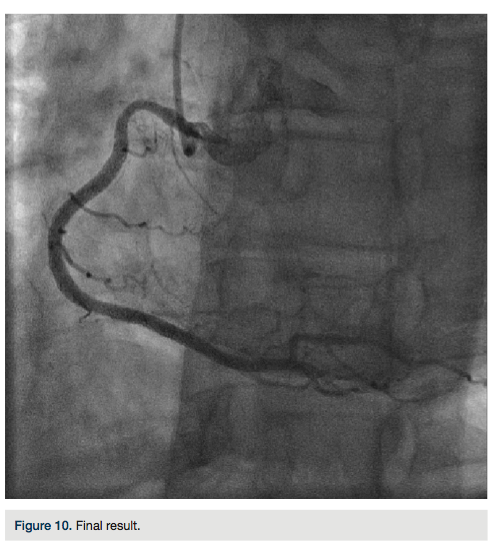

There was transient loss of flow in the posterior left ventricular branch (PLV), which was wired with a Fielder XT wire, and then changed out for a Pilot wire through an over-the-wire balloon (Figure 7). We exchanged for a Runthrough wire into the distal posterior descending coronary artery (PDA). The Corsair was removed from the collateral, and we took the guide and wire from the left system. Two additional 3.0 x 28 mm Promus drug-eluting stents were placed distally prior to the bifurcation. After stent placement, there was good flow in the distal vessel. A gap in between the stents was covered with a 3.0 x 8 mm Promus drug-eluting stent. We then

post dilated with a 3.25 x 15 mm Quantum balloon (Boston Scientific) at high pressure (Figures 8-9). Because of a pseudo lesion in the proximal vessel, we exchanged out for a Judkins right (JR) 4 guide and gave 200 mcg intracoronary (IC) nitroglycerin. Angiography revealed TIMI-3 flow in the vessel without any perforation or embolization (Figure 10). The patient tolerated the procedure well. The guide was removed and a TR Band (Terumo) was placed over bilateral radials. The patient has done well clinically, and is approximately 6 months post PCI with excellent functional capacity and no ischemic symptoms.